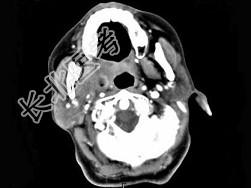

- 单项选择题女,52岁, 咽喉部疼痛半个月,伴低热, CT如图所示,最可能的诊断是 ( )

A、咽旁脓肿

B、咽部神经鞘瘤

C、鼻咽纤维血管瘤

D、咽旁淋巴瘤

E、咽旁转移瘤